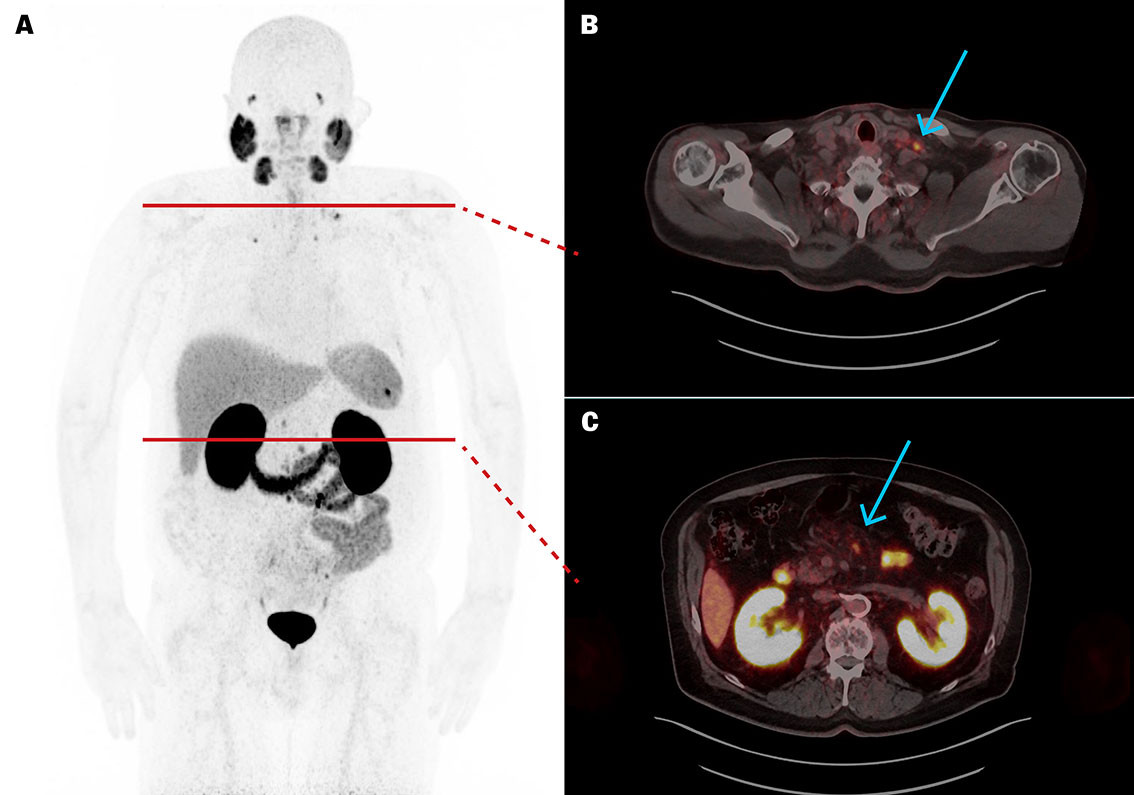

Five weeks after the fifth course of treatment, p-PSA was 1.8 µg/L. [⁶⁸Ga]PSMA-11 PET/CT revealed a significant reduction in the size of metastases (Figure 2), with the largest (target lesion) decreasing in diameter from 10 to 4 mm. Apart from decreased appetite and constipation, the treatment was well tolerated without affecting renal, salivary gland or bone marrow function.

Seven months after the fifth treatment, p-PSA had risen to 14.3 µg/L and [⁶⁸Ga]PSMA-11 PET/CT revealed new small skeletal metastases with high uptake, while lymph node metastases remained unchanged. The treatment thus had a good but temporary therapeutic effect on the metastases.